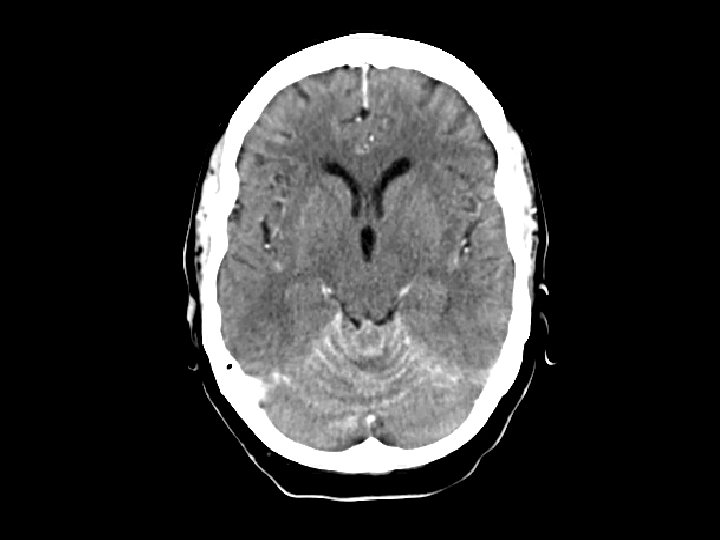

TB meningitis • Findings: – High attenuation of the cerebellar folia • Look for the primary site (lungs); usually a post-primary infection • Long and protracted illness rather an typical sx of acute bacterial meningitis • Look for BASAL involvement • ddx: – Carcinomatous meningitis – Sarcoidosis – Lymphoma – Subarachnoid blood